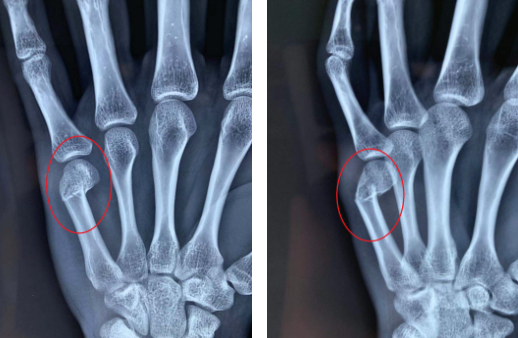

于是李某的父母立刻联系了熊祖国医生,向熊医生说明了具体情况。熊医生帮李某做了检查,又看了X线片,确诊李某是左手第五掌骨颈骨折、移位。熊医生为其进行了“顺行穿针微创”手术,手术很顺利,约30分钟完成,术后外形美观。

受伤时第五掌骨颈骨折情况